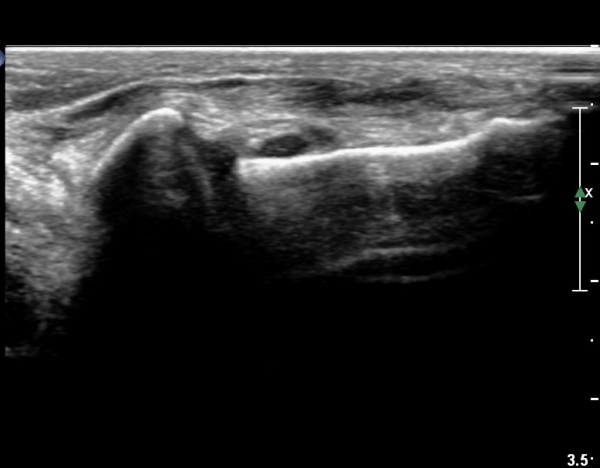

¹ß¸ñ ¾ÕÂÊ Á¾´Ü¸é°Ë»ç¿¡¼­ ¹ß¸ñ°üÀý³» °æ¹ÌÇÑ ¼ö¾×Àú·ù¸¦ º¸À̰í(»çÁø 1, 2)

°Å°ñÁÖ»ó°ñ°üÀýÀÇ ¼ö¾×Àú·ù°¡ °üÂûµÈ´Ù(»çÁø 3).

¸»´Ü °æ°ñºñ°ñÀδëÀÇ ÆÄ¿­ÀÌ °üÂûµÇ°í(»çÁø 4, 5)

ºÎÇÏ°Ë»ç ½Ã °æ°ñ°ú ºñ°ñÀÌ ¹ú¾îÁö°í ¼ö¾×ÀÇ À̵¿ÀÌ °üÂûµÈ´Ù(÷ºÎµ¿¿µ»ó 1)

Àü°Åºñ Àδë Á¾´Ü¸é°Ë»ç¿¡¼­ Àü°ÅºñÀδëÀÇ ÆÄ¿­ÀÌ °üÂûµÇ°í(»çÁø 6,7)

ºÎÇÏ°Ë»ç ½Ã °Å°ñ°ú ºñ°ñÀÌ  °úµµÇÏ°Ô ¹ú¾îÁö´Â °ÍÀÌ °üÂûµÈ´Ù(÷ºÎµ¿¿µ»ó 2)

Á¾°ñ ÀÔ¹æ°ñ Àδë Á¾´Ü¸é°Ë»ç¿¡¼­ Á¾°ñ ÀÔ¹æ°ñ ÀÎ´ë  ÆÄ¿­ÀÌ °üÂûµÇ°í(»çÁø 6,7)

ºÎÇÏ°Ë»ç ½Ã Á¾°ñ°ú ÀÔ¹æ°ñ  °úµµÇÏ°Ô ¹ú¾îÁö´Â °ÍÀÌ °üÂûµÈ´Ù(÷ºÎµ¿¿µ»ó 3)

ÃÊÀ½ÆÄ¸¦ ÀÌ¿ëÇÑ ºÎÇϰ˻ç(stress test)´Â ¹ß¸ñ ÀδëÀÇ ¾ÈÁ¤¼º(stability) À» ÆÇ´ÜÇϴµ¥

¸Å¿ì À¯¿ëÇÑ °Ë»çÀÌ´Ù.